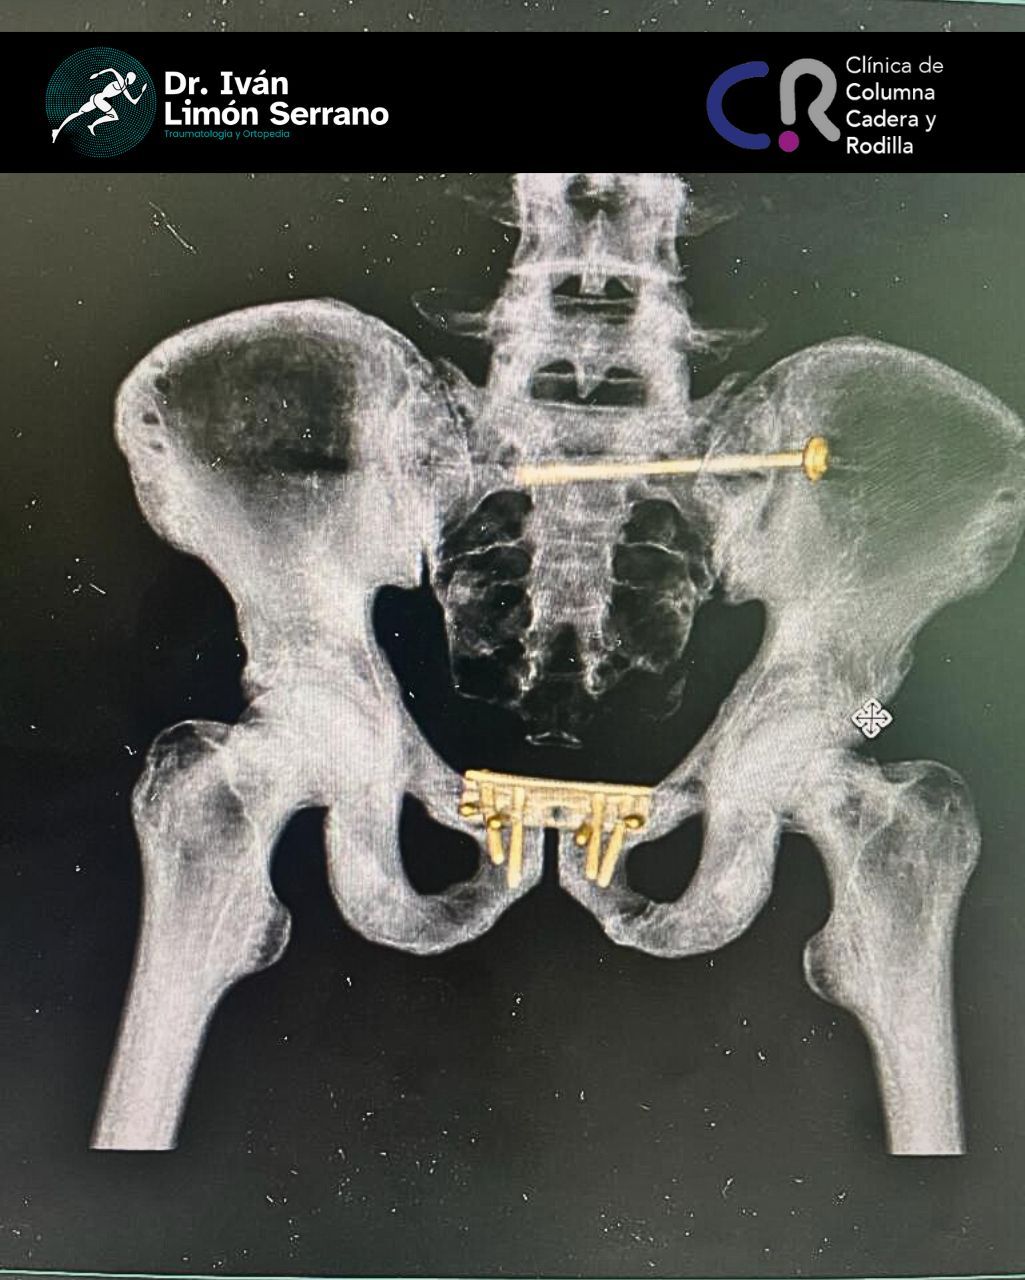

• Prótesis de cadera

• Cirugía cadera

• Artroscopia de cadera